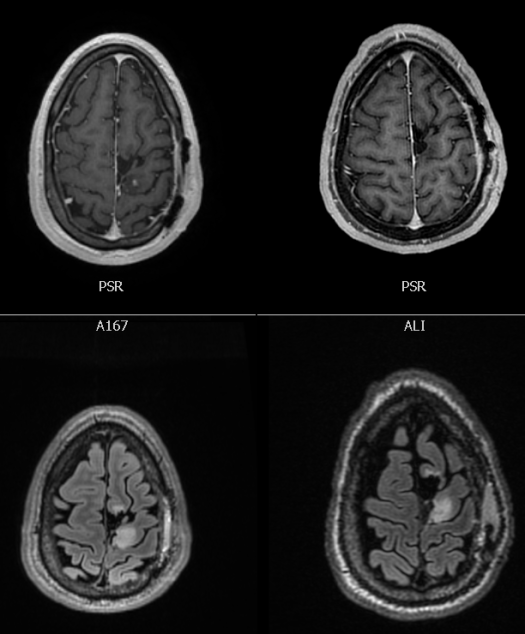

My doctor continued, “It looks like the tumor has grown. It looks denser, and in the image with contrast, there is a new spot appearing, indicating new growth.” She turned her computer screen and I looked at the MRI scans (seen below).

In these scans the brain is flipped. The tumor is in the left part of my brain (even though it appears on the right side of the image). The left side of the box are my scans from that September morning, and the right scans are from just two months prior. The top scans are images taken with contrast, which can show vascularization (new blood flow) of the tumor. If you look closely, the new scans show a little spot to the bottom-right of the resection cavity. New blood flow = tumor growth. The bottom scans show the tumor in white. The left is denser than the right, which also equates to tumor growth.

New tumor growth meant that the Enasidenib wasn’t working. It may have been fulfilling its biological role, but that alone was not enough to prevent my tumor from progressing.